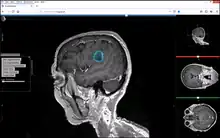

Studierfenster or StudierFenster (SF)[1][2][3] is a free, non-commercial open science client/server-based medical imaging processing online framework. It offers capabilities, like viewing medical data (computed tomography (CT), magnetic resonance imaging (MRI), etc.) in two- and three-dimensional space directly in the standard web browsers, like Google Chrome, Mozilla Firefox, Safari, and Microsoft Edge. Other functionalities are the calculation of medical metrics (dice score[4] and Hausdorff distance[5]), manual slice-by-slice outlining of structures in medical images (segmentation[6][7]), manual placing of (anatomical) landmarks in medical image data, viewing medical data in virtual reality, a facial reconstruction and registration of medical data for augmented reality,[8] one click showcases for COVID-19 and veterinary scans, and a Radiomics module.

The Metrics Module has been used to compare manual anatomical segmentations of brain tumors[30]